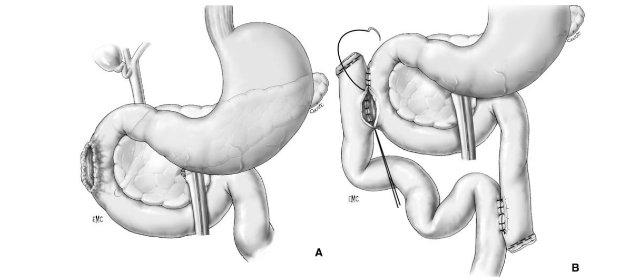

Phẫu thuật loại trừ môn vị – Pyloric exclusion procedure

Vỡ tá tràng, vỡ tuỵ không tổn thương ống tụy chính được điều trị bằng khâu tá tràng, khâu tuỵ, mở thông tá tràng qua Kehr, khâu môn vị, nối vị tràng, hút dạ dày qua dẫn lưu (theo Kenneth D. Boffard và Adam J.Brooks – 2000)

Kỹ thuật đảo dòng tá tràng (túi thừa hóa tá tràng) – duodenal diverticularization procedure

- Khâu tá tràng

- Dẫn lưu mỏm tá tràng

- Cắt hang môn vị, nối dạ dày hỗng tràng

- Cắt thần kinh X

- Dẫn lưu Kehr ống mật chủ

- Đặt hệ thống dẫn lưu cạnh tá tràng đầu tụy